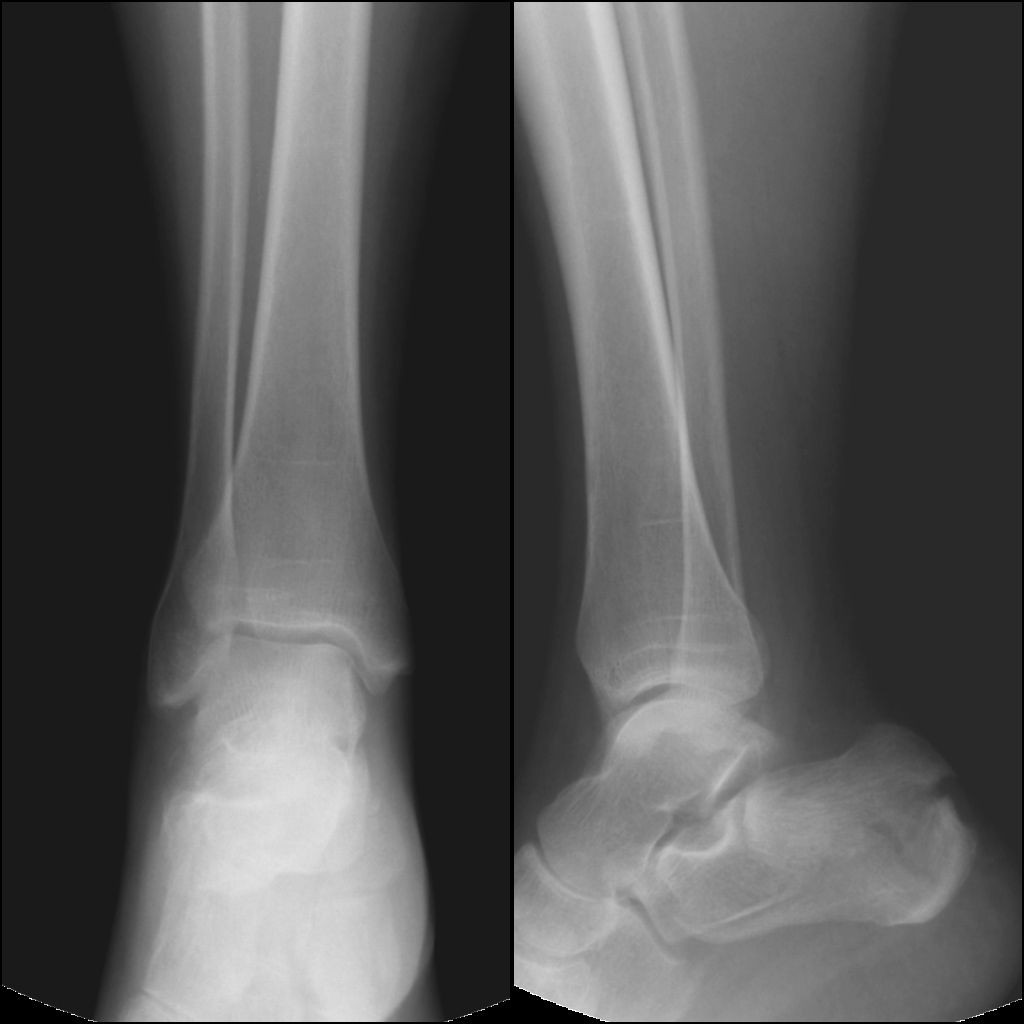

Женщина, возраст 55 лет.,вес 60кг.11.11.13 Падение с высоты 3х метров на ногу. сильная гематома на внутренней и внешней поверхности стопы. При первичном осмотре в республиканской больнице (г.Сухум) установлен диагноз: ушиб. Пациент отпущен домой.28.11.13 Сильные боли в течение двух недель.Сделан повторный рентген. Гематома спала, но полностью не рассосалась, боли уменьшились. Вторичный осмотр в военном госпитале (г.Агудзера).Диагноз: Осколочный перелом пятки со смещением.Лечение: Наложен гипс.Снимки прилагаю. Прошу помощь, по возможности, определить точность диагноза и лечения. Спасибо.

Снимок №1

Кликните для загрузки файла 3.jpg

Снимок №2

Кликните для загрузки файла 2.jpg

Снимок №3

Кликните для загрузки файла 1.jpg

Снимок 1,2,3.

Кликните для загрузки файла ALL.jpg

Перелом пятки. Если есть возможность сделать малоинвазивный остоетсоинтез - то сделать, если нет - можно и консервативное, результат должен быть удовлетворительный.